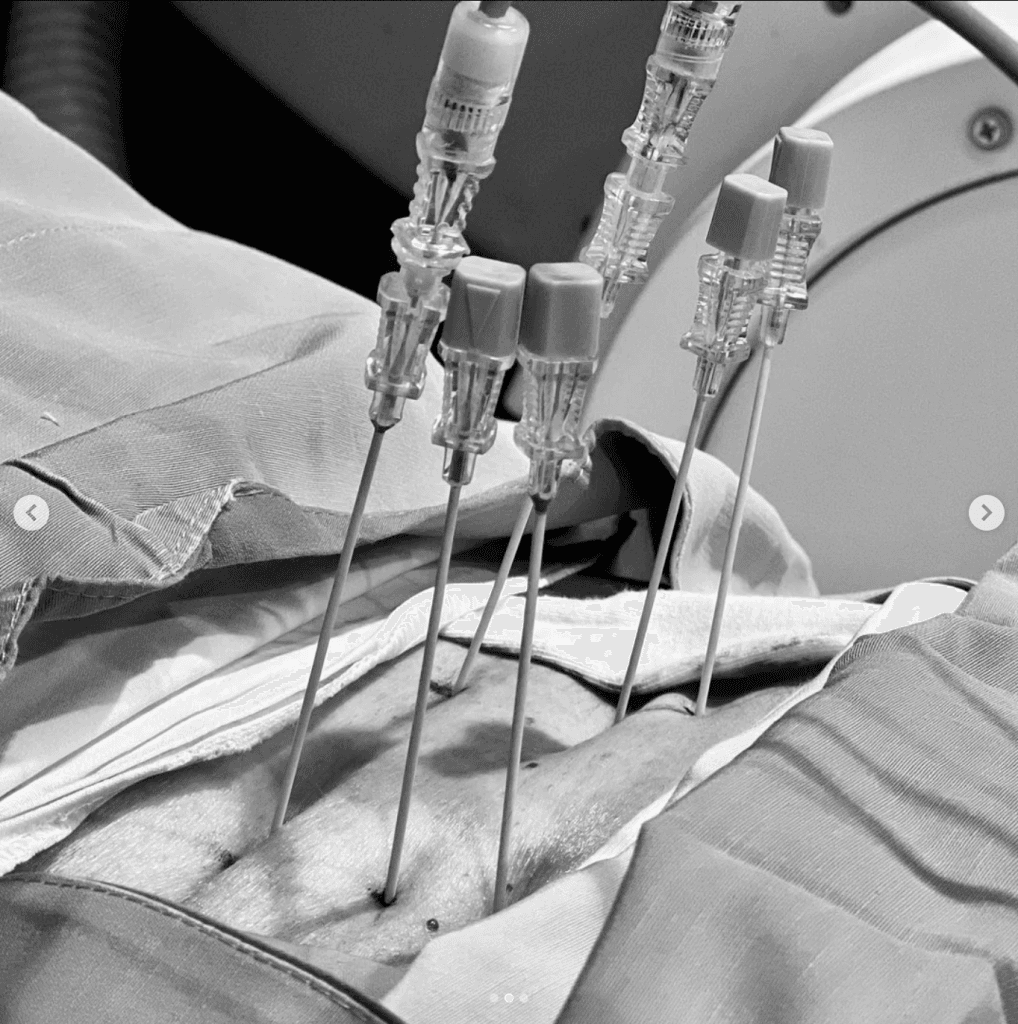

El procedimiento MAST ® MIDLF ™ utiliza un conjunto de tecnologías que permiten y facilitan un enfoque anatómico de la

Leer más